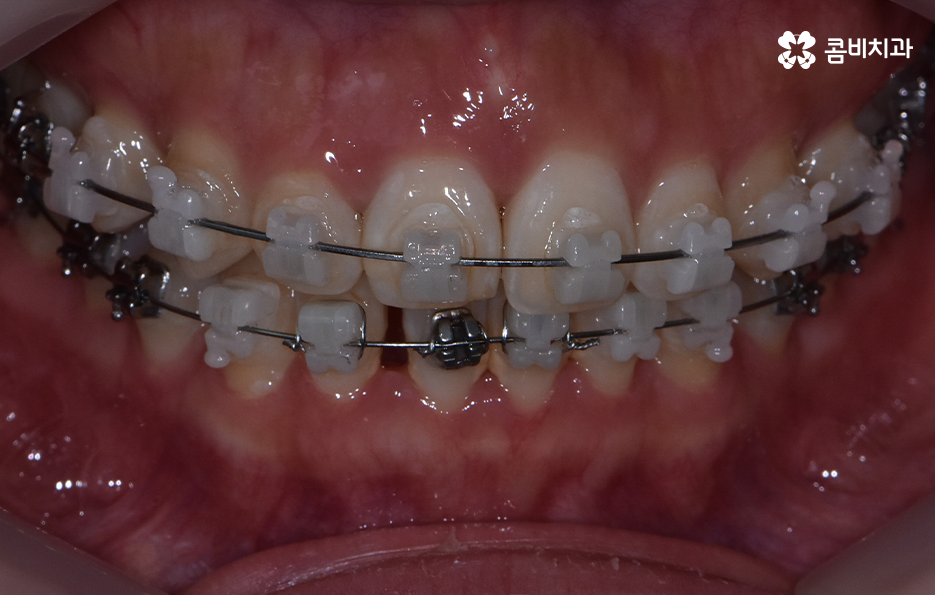

교정 치료는 크게 발치와 비발치치아교정으로 나뉠 수 있는데 비발치치아교정의 경우에는 아무래도 치아가 움직이는 양도 적고 그에 따라 교정 기간도 짧은 편에 해당되고 있어요.

교정을 하게 되면 아무래도 치아와 잇몸이 함께 움직이기 때문에 어느정도는 잇몸이 약해질 가능성이 있는데 비발치치아교정의 경우에는 치아의 이동이 큰 편은 아니기 때문에 발치교정에 비해서는 잇몸이 약해지는 정도 및 확률이 줄어들 수 있어요

반면에 발치교정의 경우에는 최소 1년 6개월 ~ 2년 이상의 교정 기간이 소요되며 치아가 빠진 공간에 나머지 치아들이 메우면서 치아의 이동이 비발치치아교정에 비해 많기 때문에 그에 따라 치아는 물론 치조골의 이동도 감안해야 하므로 치료 기간도 더 오래 걸리고 잇몸도 좀더 약해질 수 있는 확률이 발치교정에 비해서는 높은 편으로 볼 수 있는데요.